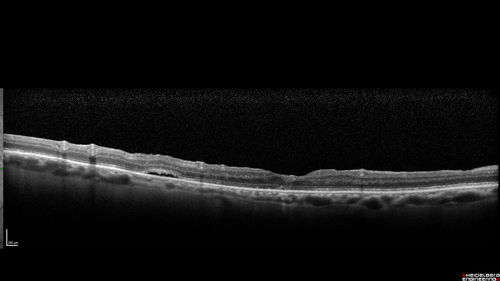

Macular Hole with Limited Retinal Detachment - 6 months post-op

87 year old female with decreased vision in the left eye for 2 months.  VA 5/200.  Initial three images are pre-op.  Then there is 3 months 6 months and 9 months post-op scans.  VA improved at 1 year to 20/50.  Surgery was done with Brilliant Blue.